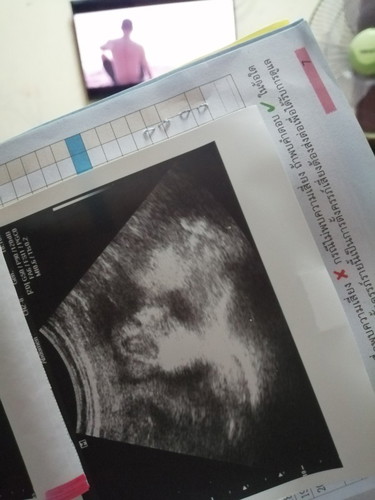

บ้านนี้ท้องลูกสาว ตอนนี้ 33 weeks นน.น้องมี 2,261 กรัม กำหนดคลอดประมาณวันที่ 22 พย. แม่ๆบ้านไหน คลอดเดือน พย. เหมือนกันบ้าง นน.น้องเท่าไหร่กันบ้างแล้วคะ